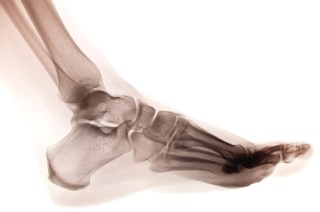

I have a couple of questions for you about a broken foot. In my WIP, my main male character broke his foot. About how long would it be before he could be up on stage in a rock concert? He’s the lead guitarist of a Christian rock band and is quite active during the show (running around, etc).

First, I’m assuming you mean a bone in the foot is actually broken and not the toe itself.